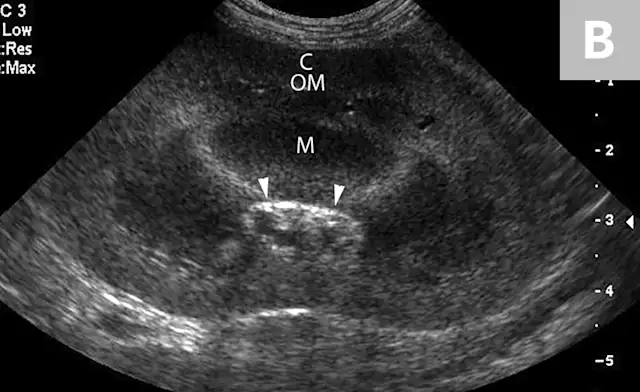

FIGURE 6A

Mild to moderate right hydronephrosis and proximal ureteral dilation in a Dalmatian.

Clinical signs associated with ureteral calculi may range from chronic non-specific signs to acute or chronic renal failure. The presence of hydronephrosis can be highly suggestive of a ureteral obstruction (Figure 6).